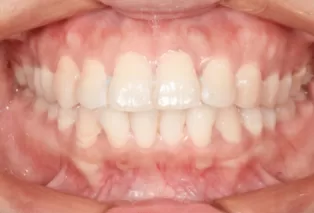

Intraoral photos after treatment